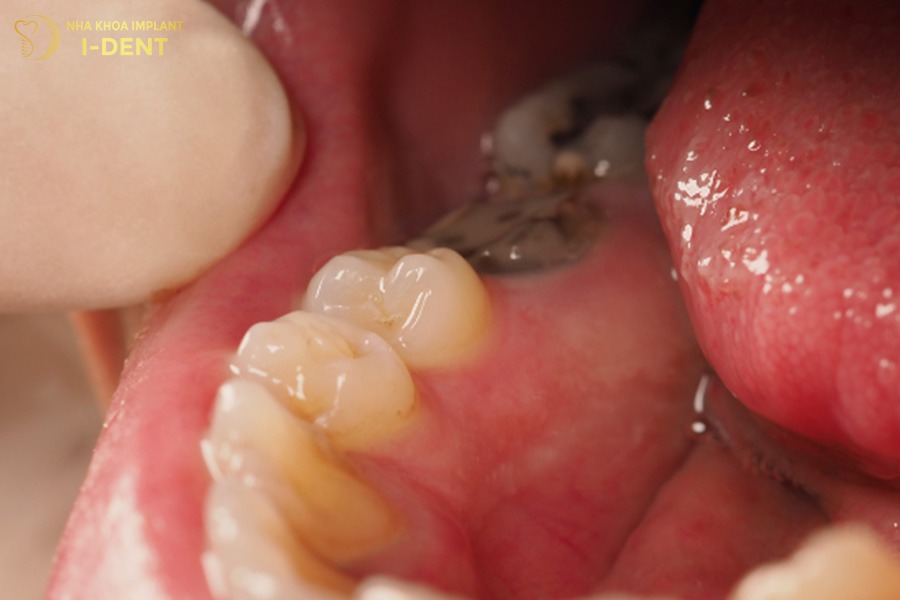

3.3. Viêm nhiễm răng miệng

Khoảng trống do mất răng số 6 lâu năm là nơi dễ tích tụ thức ăn và mảng bám tạo điều kiện cho vi khuẩn phát triển. Nếu không vệ sinh kỹ thì tình trạng này sẽ dẫn đến viêm lợi, hôi miệng và sâu răng lan sang các răng kế cận.

Ngoài ra, mất răng số 6 mà không điều trị kịp thời còn khiến mô nướu và tủy răng dễ bị viêm nhiễm, gây đau nhức âm ỉ trong vòm miệng. Bệnh nhân có thể gặp tình trạng nướu sưng tấy, chảy máu thường xuyên khi chải răng hoặc xỉa răng, làm suy giảm sức khỏe răng miệng và làm tăng nguy cơ mất thêm các răng khác.

Mất răng số 6 lâu năm gây viêm nhiễm răng miệng.